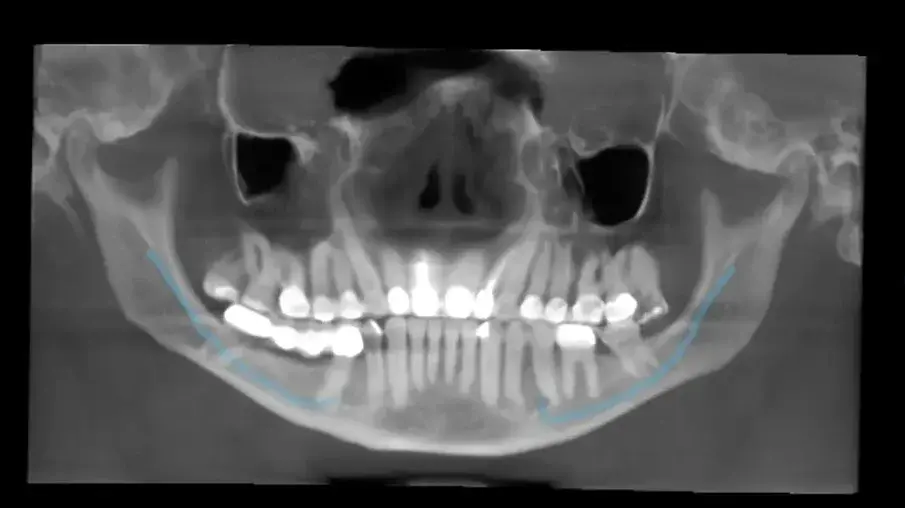

Помолих да се направи i-CAT скенер, за да разбера по-добре каква е ситуацията. Изучавайки хоризонталния изглед на 3D изображението, ясно се виждаше нивото на калцификация в пулпната камера в сравнение с пулпната камера на първия молар (фиг. 2).

Фиг. 2 Хоризонтален напречен разрез, направен от i-CAT сканирането (DEXIS), показващ пълна калцификация на орифициумите на нивото на цименто-емайловата граница в сравнение с първия молар.